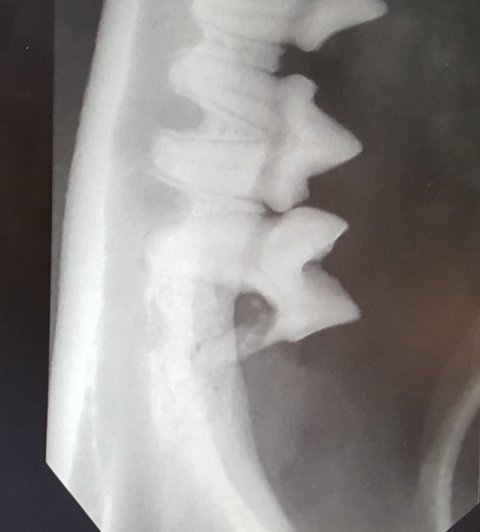

점박이의 발치된 부분의 엑스레이 사진입니다.

엑스레이 사진의 아랫부분의 이빨이 뻥 뚫려서 공동이 생겨 있습니다.

이 이빨도 발치를 했습니다.